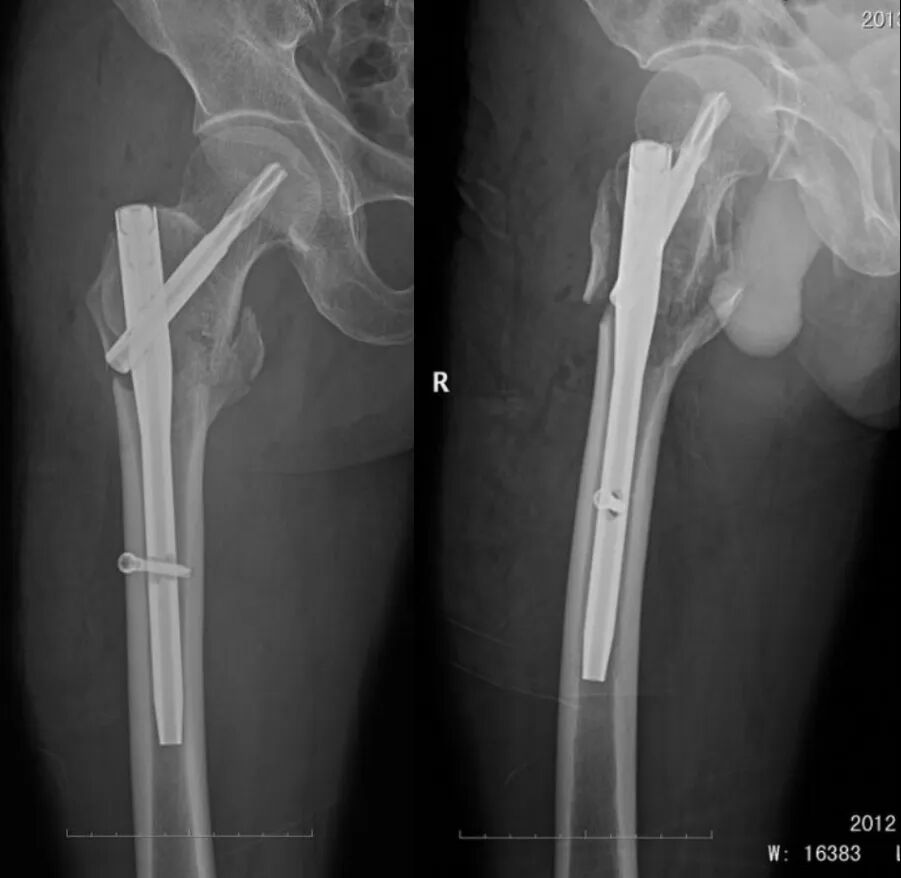

手术后 X 线片

术后 21 个月 X 线片:

患者术后一年半有余,要求去除内固定物来院,未诉不适,大意了,术前阅片不仔细,术中拆除锁钉、螺旋刀片和尾帽,拔主钉后傻眼了 —— 只拔出了上三分之一 ,回头再看片子才发现主钉刚好在螺旋刀片处断裂了。

之前就看骨折愈合得很好,时间也够,当小菜一碟,没有仔细阅片,术中很是被动,想过取,感觉创伤太大,仔细与患者沟通,建议患者不取了,家属也签字了,结果术后还是纠缠不休,最后免费治疗,赔钱走人。教训是惨痛的啊!